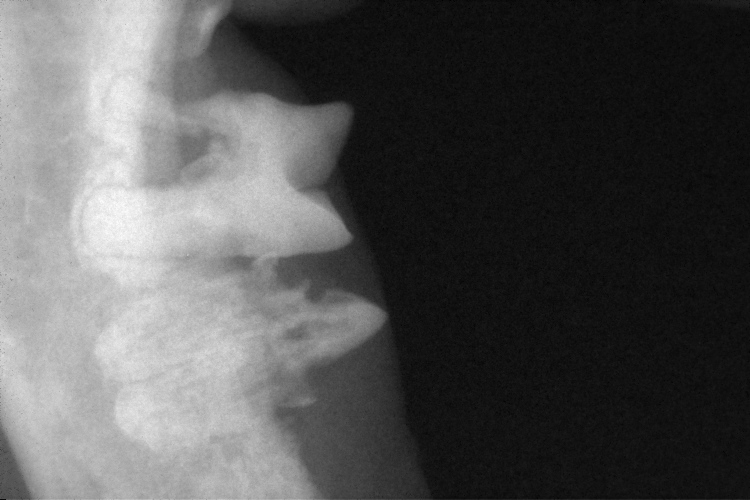

右下顎第2前臼歯(写真上側の歯)と第1後臼歯(写真下側の歯)です。

第2前臼歯は近心根が細くなり(黄色矢印)、吸収している事が確認出来ます。

第1後臼歯は歯冠が吸収し(黄色〇)、歯根はアンキローシスを起こしていました。